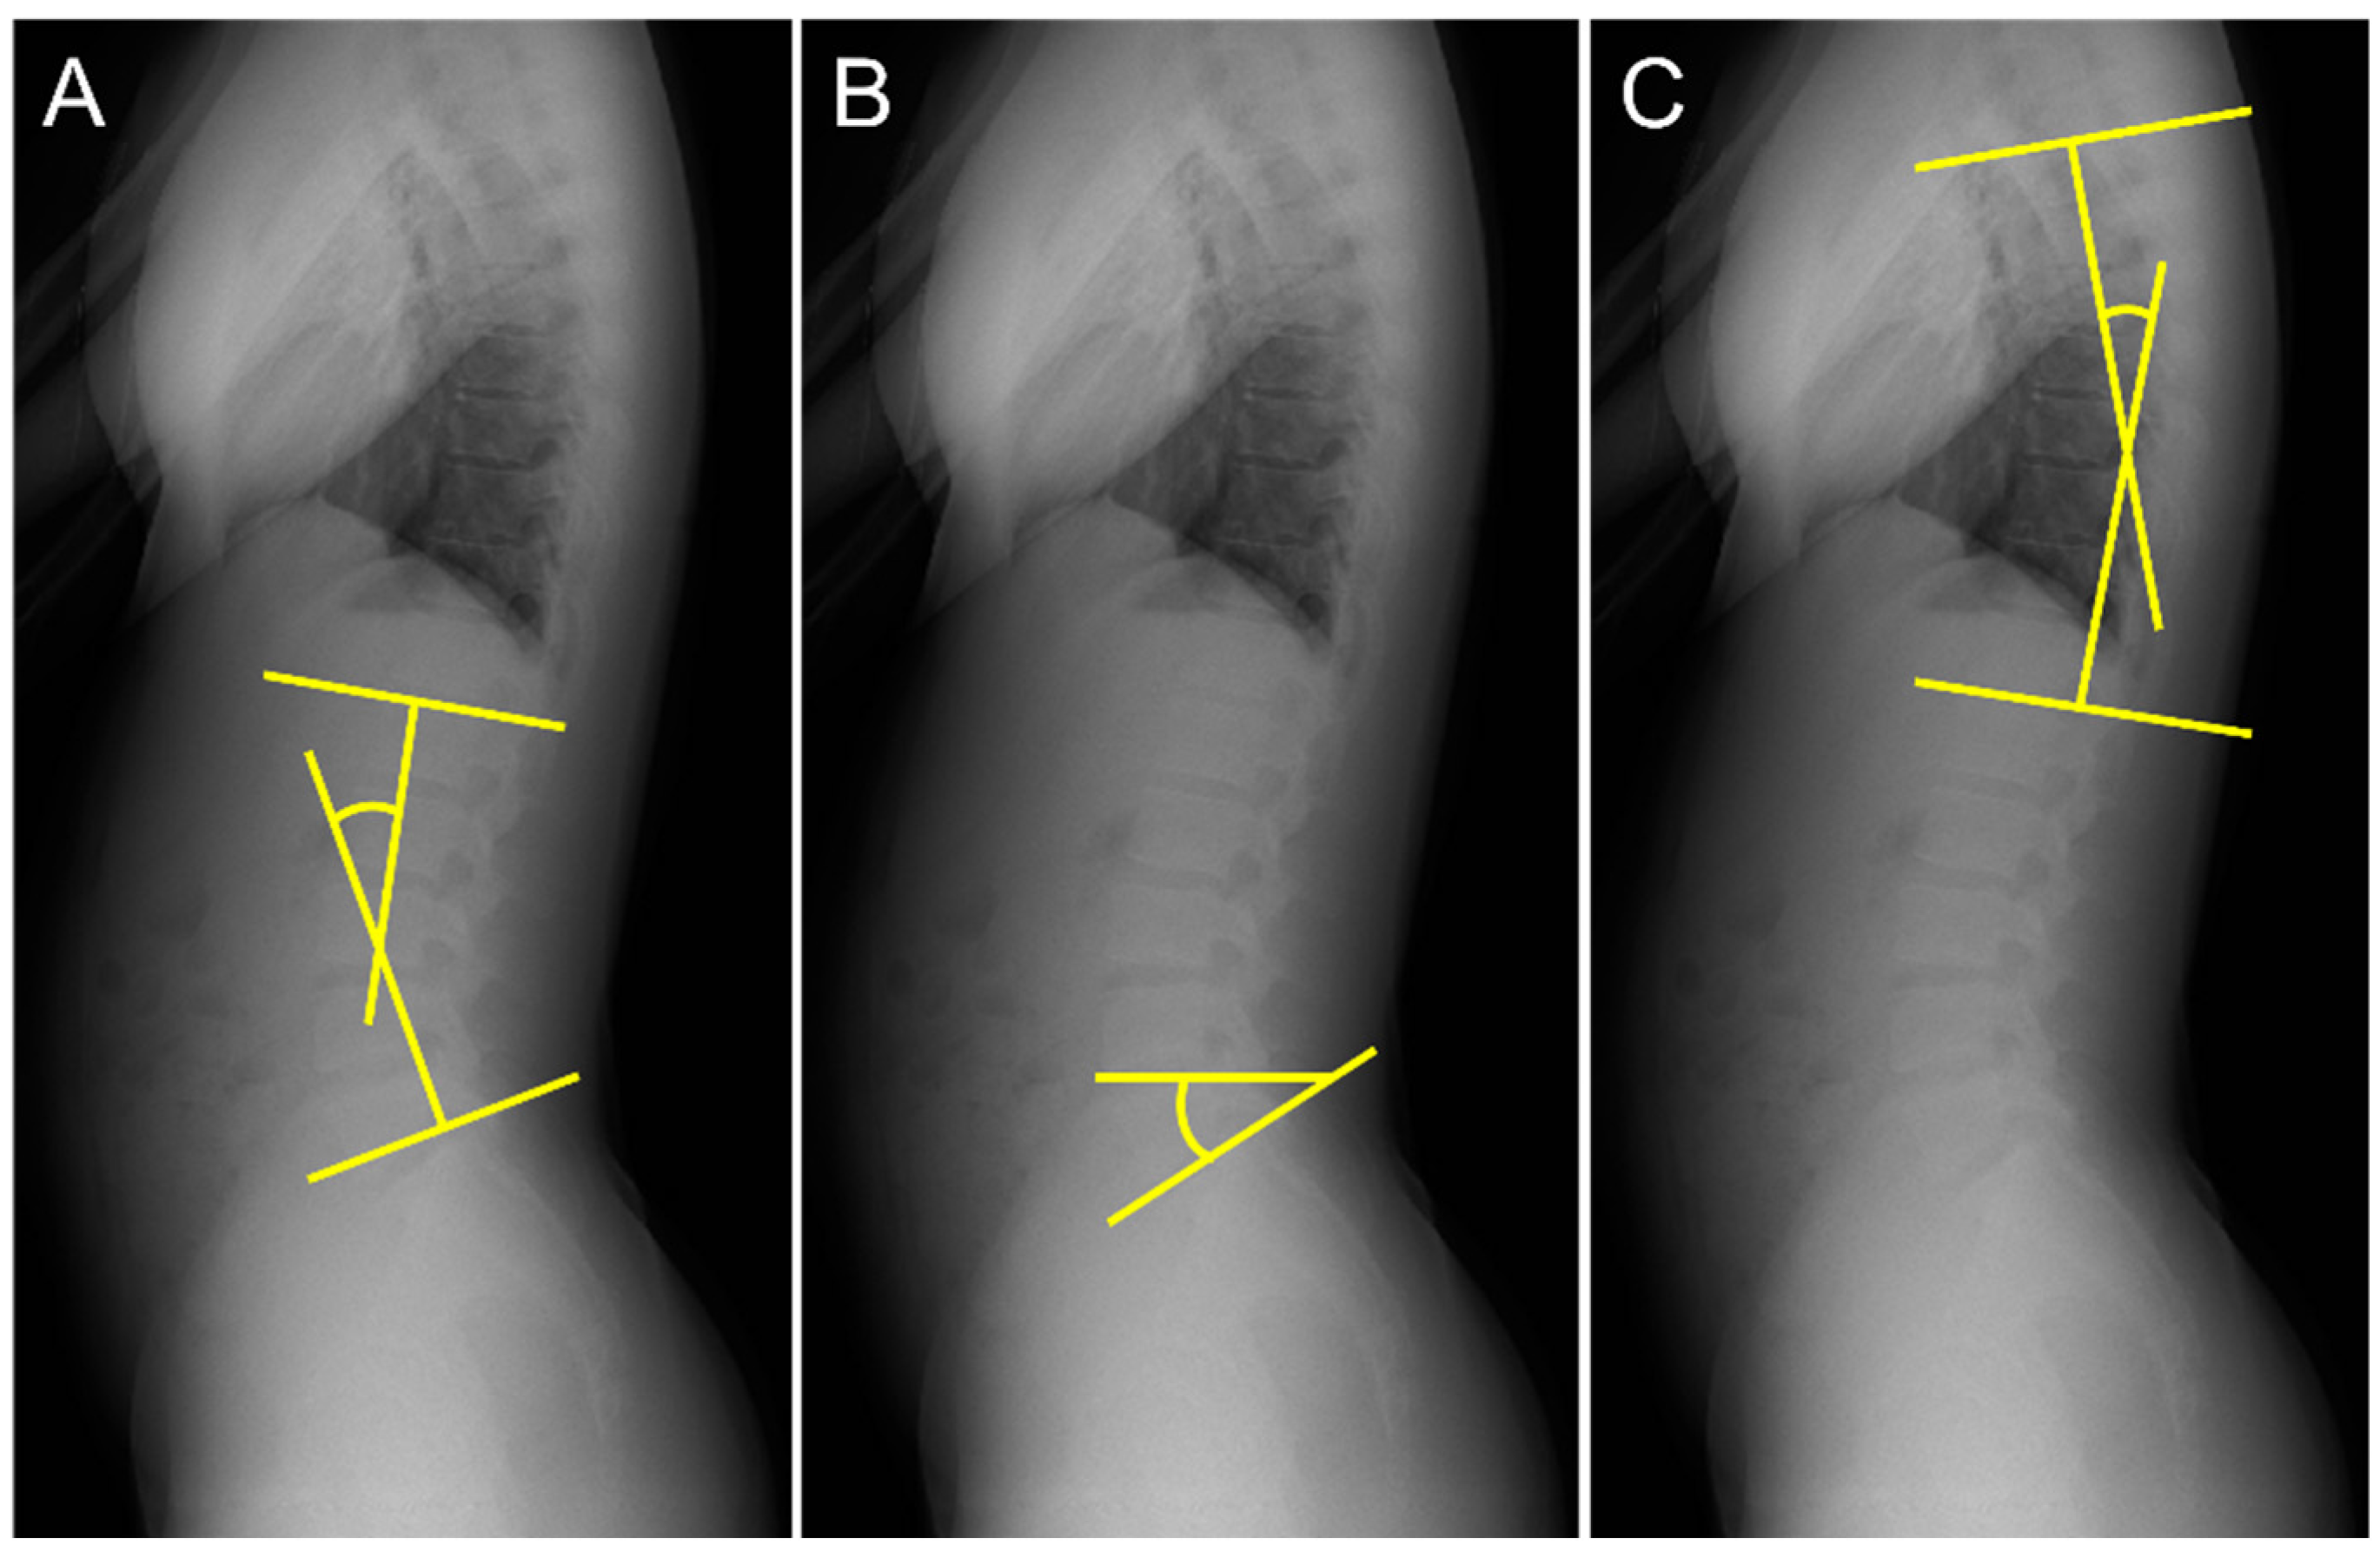

| Lumbar lordosis angle (LL, °) | Standing | 36.9 ± 5.1 a | 29.0 ± 5.2 |

| Elevation position | 39.9 ± 7.9 a | 30.5 ± 4.7 | |

| Sacral slope angle (SS, °) | Standing | 35.1 ± 6.4 b | 26.9 ± 5.3 c |

| Elevation position | 36.6 ± 5.8 | 31.8 ± 6.3 | |

| Thoracic kyphosis angle (TK, °) | Standing | 22.1 ± 5.2 | 23.4 ± 3.8 |